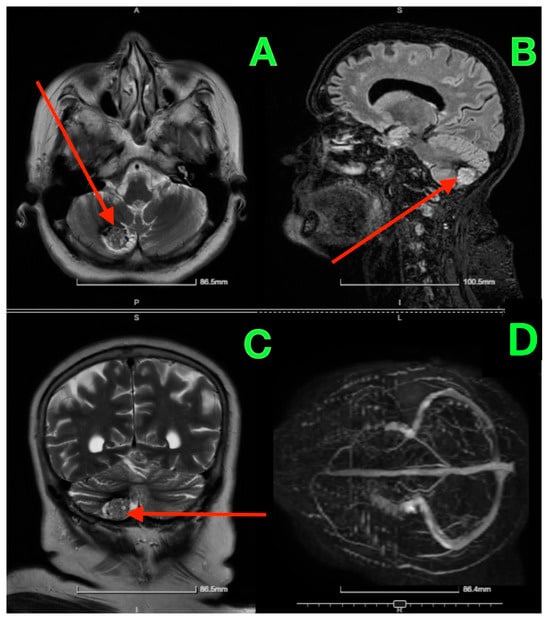

Given the patient’s symptoms and neurological findings, an MRI scan of the brain was performed to further evaluate potential cerebellar or vestibular pathology. The MRI revealed a well-circumscribed cavernous malformation (cavernoma) located in the right cerebellar hemisphere (Figure 1 and Figure 2). The lesion appeared hyperintense on T2-weighted imaging, with a peripheral rim of hemosiderin, suggestive of prior microhemorrhages. The lesion measured approximately 1.5 cm in diameter and was localized to the posterior fossa, without any evidence of acute hemorrhage or mass effect. The surrounding cerebellar structures, including the brainstem, showed no significant compression or deviation. Magnetic resonance angiography (MRA), performed to rule out vascular anomalies, confirmed the absence of arteriovenous malformations or other vascular abnormalities (Figure 1D and Figure 2D). The lesion was determined to be isolated, with no direct involvement of the major cerebellar arteries or veins.

Figure 1. Pre-op MRI scan. (A) (Axial T2-weighted MRI): Displays the lesion in the right cerebellar hemisphere, highlighted by the red arrow, which points to a hyperintense core surrounded by hemosiderin deposition at the periphery, consistent with a cavernous malformation. (B) (Sagittal T2-weighted MRI): The red arrow indicates the location of the lesion in the posterior fossa, situated near the cerebellar hemisphere, without significant impact on the cerebellar vermis or brainstem. (C) (Coronal T2-weighted MRI): The red arrow emphasizes the lesion’s size and well-defined borders relative to the surrounding cerebellar tissue, confirming the absence of surrounding edema. (D) (MRA Axial View): No red arrow is present as this image confirms the absence of any vascular abnormalities in proximity to the lesion.